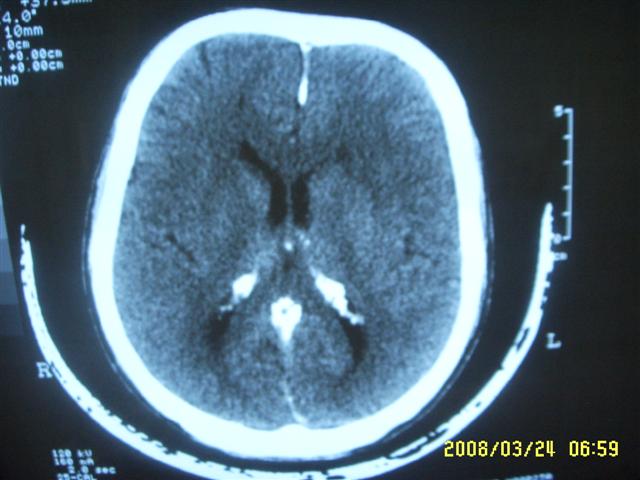

以下是引用dyqct在2008-4-2 20:09:00的发言:[br]考虑为:神经纤维瘤病(nf1型)。建议增强进一步检查。